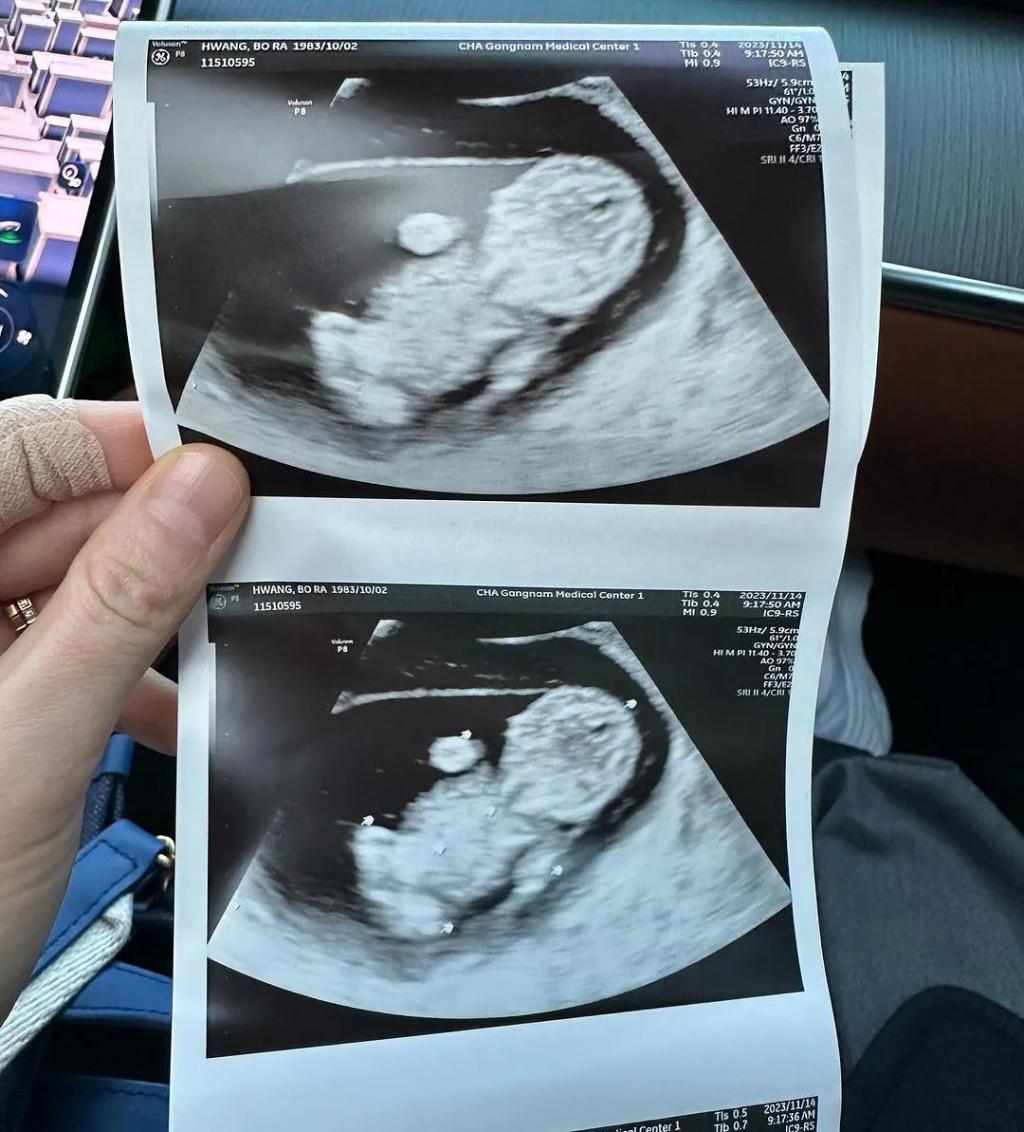

黄宝拉也通过个人社交平台分享了这则喜讯,还公开了胎儿的超声波照片,表示:" 结婚正好一周年,上帝赐予了我们夫妇一个小天使 "。